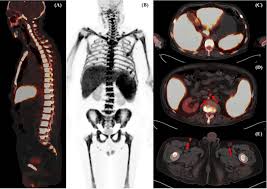

An FDG PET CT scan uses a radioactive glucose tracer (FDG) to identify areas of abnormal metabolic activity in the body. Cancer cells tend to consume more glucose than normal cells, making this scan extremely effective for early detection and disease monitoring. The Best FDG PET CT Scan in Greater Kailash helps doctors detect conditions that may not be visible on conventional imaging tests.

The Best FDG PET CT Scan in Greater Kailash is supported by advanced PET CT scanners that provide high-resolution images and precise metabolic mapping. Modern equipment ensures better detection of even small lesions, leading to early and accurate diagnosis.